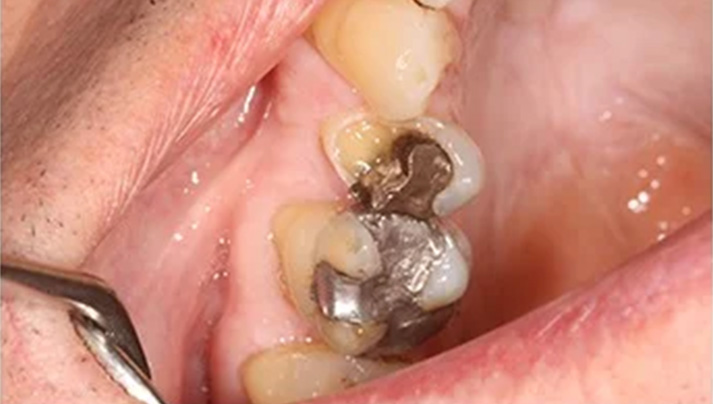

Before and Afters – White Fillings